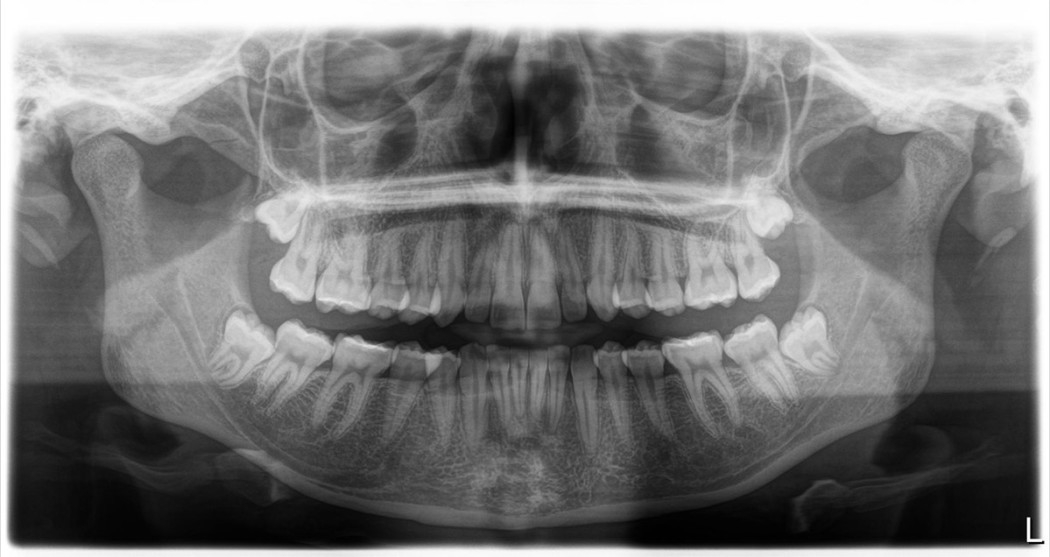

La imagen de rayos X muestra al paciente (mujer, 22 años) con la siguiente indicación: Búsqueda de enfoque - 8. Hallazgos: La OPG muestra una dentición sana y sin caries. Las muelas del juicio 18, 28, 38 y 48 están impactadas. Las articulaciones mandibulares son iguales en ambos lados, los senos maxilares son simétricos y, hasta donde se puede ver en la OPG, también son normales. No se encontraron estructuras patológicas.